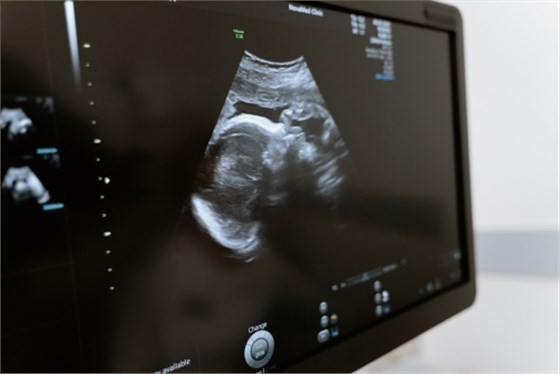

產前檢查通常在孕早期、孕中期、孕晚期進行,用于孕婦及胎兒的健康檢查。產前檢查一般包括四維彩超、胎兒彩超、糖尿病篩查、唐氏篩查等,應按照產檢要求及時進行相應檢查。

1、四維彩超:四維彩超在孕中期可用于篩查胎兒存在的各類畸形,如面部畸形、脊柱畸形、腦積水、唇腭裂、無腦兒、脊柱裂臟器外翻等。還可觀察到胎兒是否存在先天性心臟病,以及多囊腎、腎積水、腦積水、腦膜膨出、脊柱裂等疾病;

2、胎兒彩超:胎兒彩超可用于觀察胎兒的大小、形態、羊水、胎盤,以及胎兒是否存在臍帶繞頸等情況;